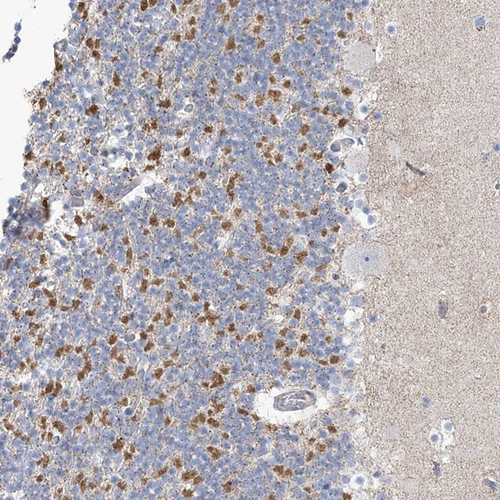

HPA035434

methylenetetrahydrofolate dehydrogenase (NADP+ dependent) 2-like

Anti-MTHFD2L Antibody

Polyclonal Antibody against HUMAN MTHFD2L